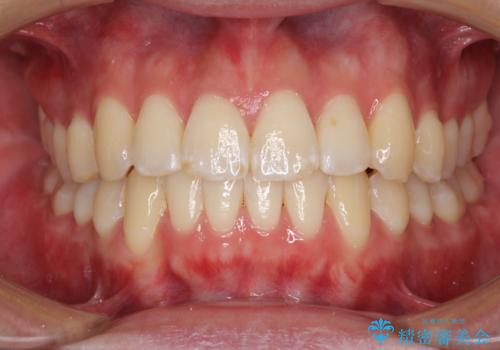

[インビザライン ライト] 短期間(3.5ヶ月)で終わるマウスピース矯正

![[インビザライン ライト] 短期間(3.5ヶ月)で終わるマウスピース矯正の症例 治療後](https://seimitsushinbi.jp/wp/wp-content/uploads/2020/02/2f36cdf472a802b537022ae239b8cb6b-500x350.jpg?v=1580813669)